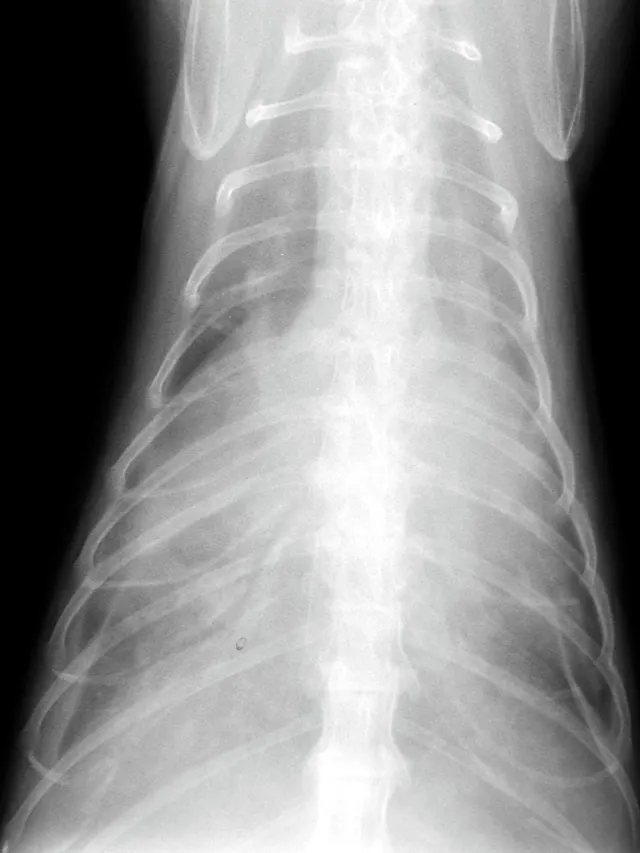

Once the patient is stabilized (often after 12 to 24 H), obtain radiographs (Figure 3) and echocardiography to confirm the diagnosis of CHF and to identify the nature and severity of the cardiac disease. The most common cause of CHF in cats is HCM; less common are dilated, restrictive, and unclassified cardiomyopathy. Murmurs associated with HCM are usually created by mitral regurgitation, abnormal displacement of the mitral valve during systole (systolic anterior motion or SAM), causing left ventricular outflow tract obstruction, or dynamic right ventricular obstruction either in combination (e.g., mitral regurgitation is always present with SAM) or alone (mitral regurgitation can also occur without SAM) (Figure 4).

FIGURE 3 Lateral (A) and dorsoventral (B) radiograph of a cat with pleural effusion and suspected cardiomegaly; the radiograph was obtained after stabilization.